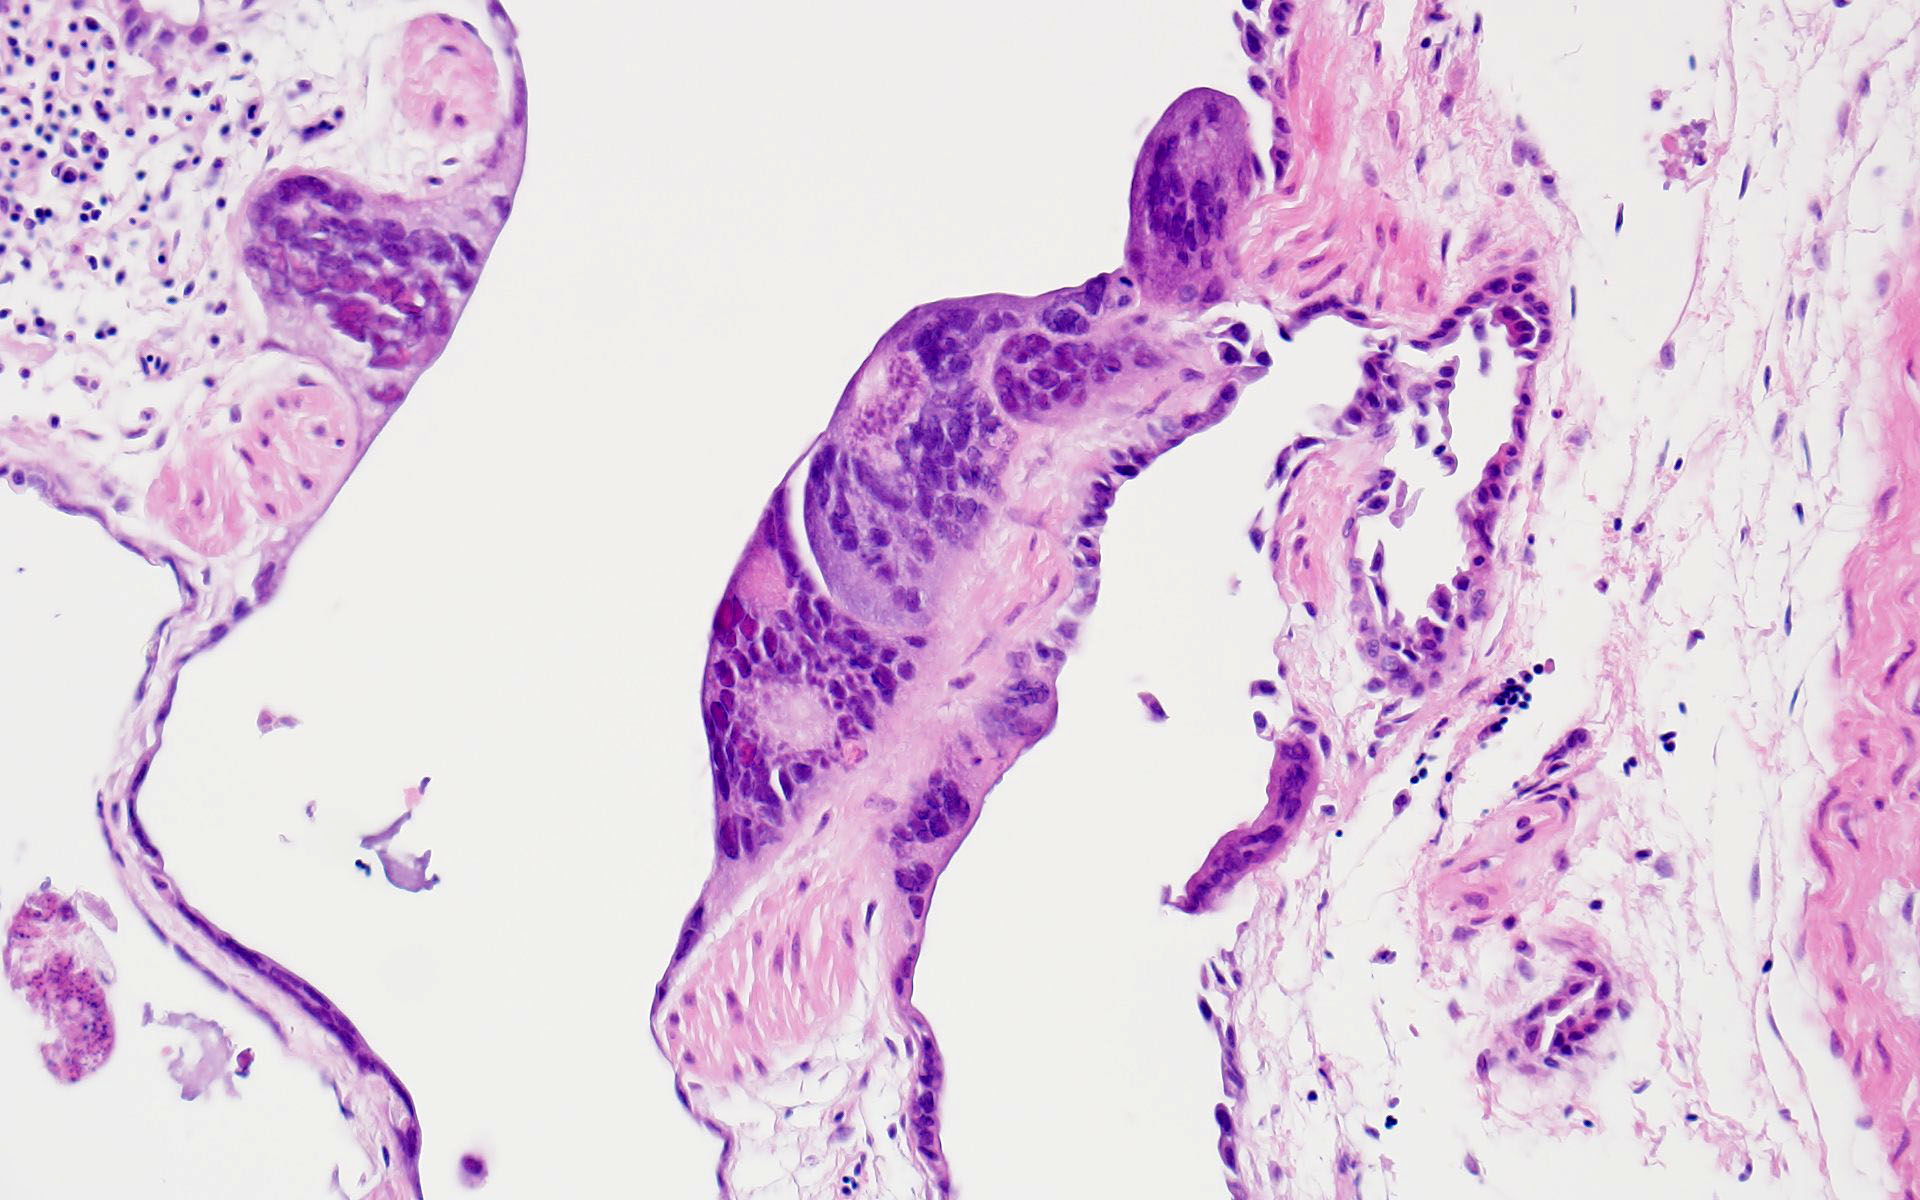

The bronchi and parabronchi contain numerous large syncytia with large amphophilic-to-eosinophilic intranuclear inclusions that marginalize the chromatin. Bronchi and parabronchi also often contain foamy macrophages, pale basophilic mucus, homogeneously eosinophilic edema fluid, fibrin, cellular debris, and sloughed necrotic epithelial cells.

The JPC’s own Dr. Elise LaDouceur moder-ated this year’s avian-focused seventeenth conference. This first case provided participants with a panoply/salmagundi/”dog’s breakfast” of tissues to sort through to achieve a diagnosis. The characteristic intranuclear viral inclusion bodies of herpesvirus were best seen in the air sac respiratory epithelium, which also rewarded conference-goers with some exceptional viral syncytia. Of the potential herpesviral culprits, psittacine al-phaherpesviruses (PsAHV) 1, 3, and 5 have been reported in psittacine species, including Indian ringneck parakeets, and PsAHV-5 was isolated by the contributor in this case. The contributor provided some beautiful electron microscopy (EM) photos from this bird that demonstrated intranuclear herpesviral virions, with some virions budding from the nuclear envelope to become enveloped themselves, and others hanging around the rough endo-plasmic reticulum (RER) to acquire additional proteins. The JPC is grateful to the contributor for providing these excellent educational images!